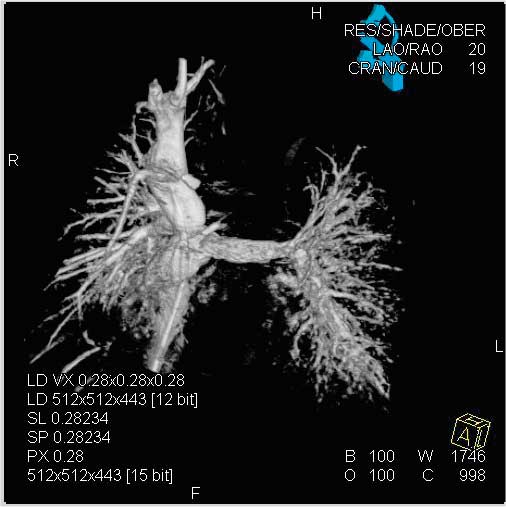

Figure

Figure 1. Hypoplastic left heart syndrome: Intraoperative post-Fontan evaluation of the superior and inferior venae cavae and the stented pulmonary arteries.Courtesy of Prof. Berger, Dr. Ewert Deutsches Herzzentrum, Berlin, Germany

Although surgery remains the treatment of choice for many congenital cardiac malformations, interventional cardiology approaches are increasingly being used in simple and even complex lesions. The percutaneous approach can be challenging due to low patient weight or poor vascular access, induced rhythm disturbances and hemodynamic compromise (2). Difficult and complex anatomy as in double-outlet right ventricle or transposition of the great arteries, or acute turns or kinks in the pulmonary arteries of tetralogy of Fallot patients can make percutaneous procedures challenging if not impossible (19). On the other hand, surgery also has its limitation. Examples are operative closure of multiple apical muscular ventricular septal defects, adequate and lasting relief of peripheral pulmonic stenosis, or management of a previously implanted stenotic stent. Combining interventions and surgery into a single therapeutic procedure leads to reduction of complexity, cardiopulmonary bypass time, risk, and improved outcomes. The hybrid approach to hypoplastic left heart syndrome serves as a role model of the concept (Figure 1) (1, 10).